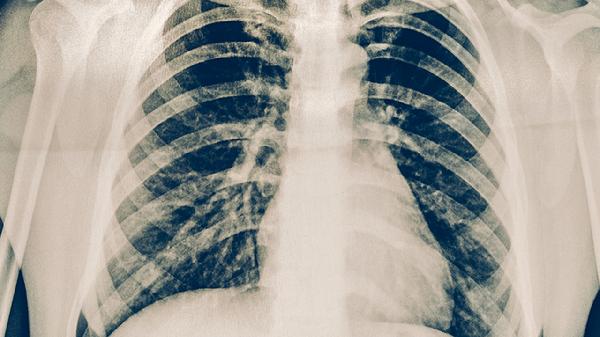

肺結(jié)核是由結(jié)核分枝桿菌引起的慢性傳染病,主要累及肺部但可波及全身器官,典型癥狀包括咳嗽、咯血、低熱和盜汗。肺結(jié)核的基本常識(shí)主要有傳播途徑、易感人群、典型癥狀、診斷方法和規(guī)范治療五方面。

痰涂片抗酸染色鏡檢是基礎(chǔ)篩查手段,痰培養(yǎng)可提高檢出率但耗時(shí)較長(zhǎng)。胸部X線或CT檢查能發(fā)現(xiàn)肺部典型病變。γ-干擾素釋放試驗(yàn)等新型檢測(cè)方法特異性較高。確診需結(jié)合臨床表現(xiàn)、影像學(xué)檢查和病原學(xué)證據(jù)。